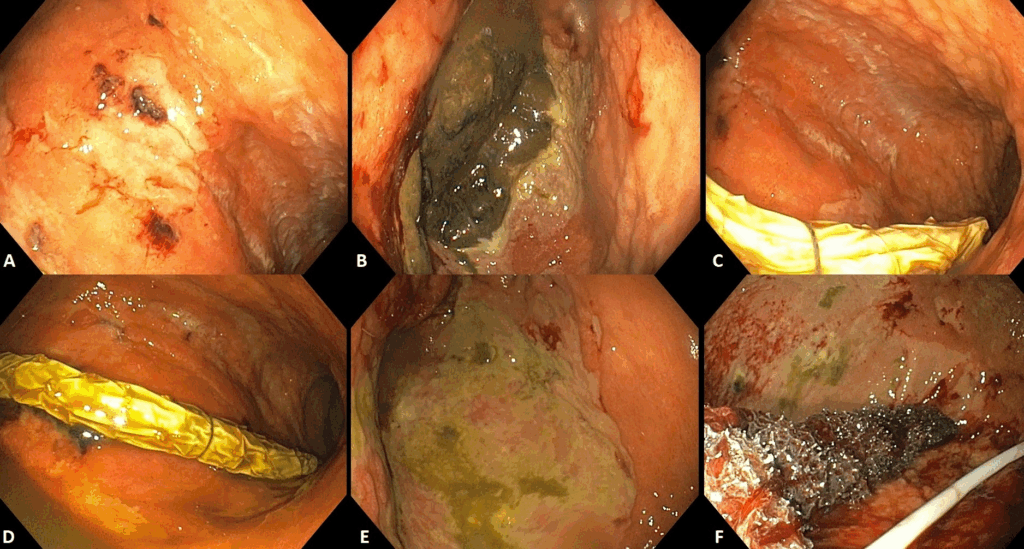

Figura 3 Adaptado de Dall’Agnol et al (9):

A-C: 7 dias de TEV

D-F: 14 dias de TEV